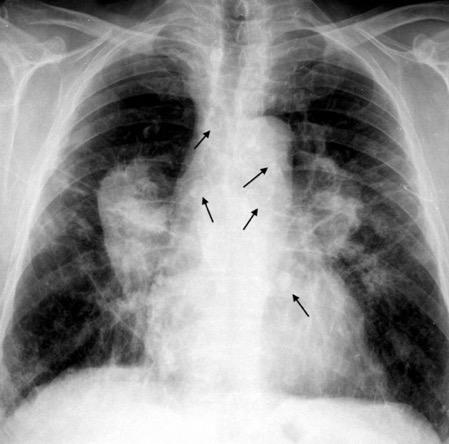

Neumoconiosis

Gross GH et al. Egg-Shell calcification of lymph nodes. An update. AJR 1980

Silicosis (5%)

Neumoconiosis del carbón (1,3-6%)

Sarcoidosis. ( 5%)

Hongos y bacterias. Tuberculosis. Cocidioidomicosis

Histoplasmosis

Amiloidosis Idiopática

Silicosis

Grayson CE et al. Egg Shell calcification in silicosis. Radiology 1949

Silicosis secundaria al pulido con chorro de arena. Tejidos ”Denim”. (vaqueros, etc.)

Marchiori E et al. Conglomerated masses of silicosis in sandblasters: High-resolution CT findings. Eur Radiol 2006

Alper F,, et al. CT findings in silicosis due to denim sandblasting. Eur Radiol. 2008